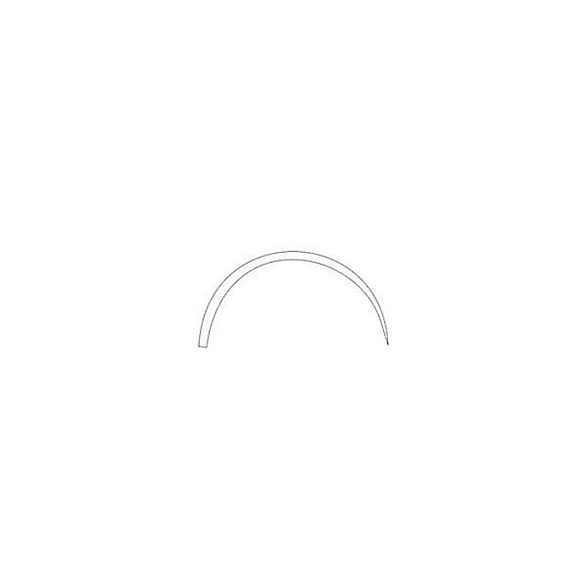

Игла с изгибом 4/8 (полукруглая) и трёхгранной заточкой 4А1 обеспечивает минимальную травматичность тканей и максимальный контроль при проколе. Изготовленная из высококачественной нержавеющей стали, она гарантирует прочность, стерильность и многократное использование после соответствующей обработки.

- Форма изгиба 4/8 (3/8 круга): Оптимальный изгиб для работы в глубоких и труднодоступных ранах. Позволяет выполнять точные и аккуратные проколы с минимальным усилием, обеспечивая хирургу отличный обзор и контроль над движением.

| Тип изгиба | 4/8 (полукруглая, 3/8 круга) |

Цифры обозначают часть круга, которую описывает изгиб иглы. 4/8 — это половина круга (полукруглая), 3/8 — меньший изгиб, 1/2 — аналогично 4/8. Изгиб 4/8 является одним из самых распространенных и универсальных для работы в глубине раны.